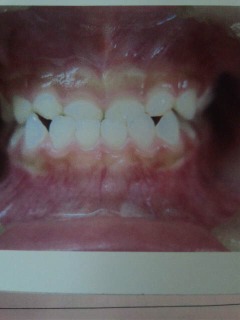

痛くない!?

はっきり虫歯とわかる虫歯です。しかも前歯です。こんな状態でも痛くなかったからと言われ、歯医者の力不足を反省!痛くならないと来院されない患者さんに歯医者ができることは?いろいろ考えるお盆休み、16日まで診療お休みです。